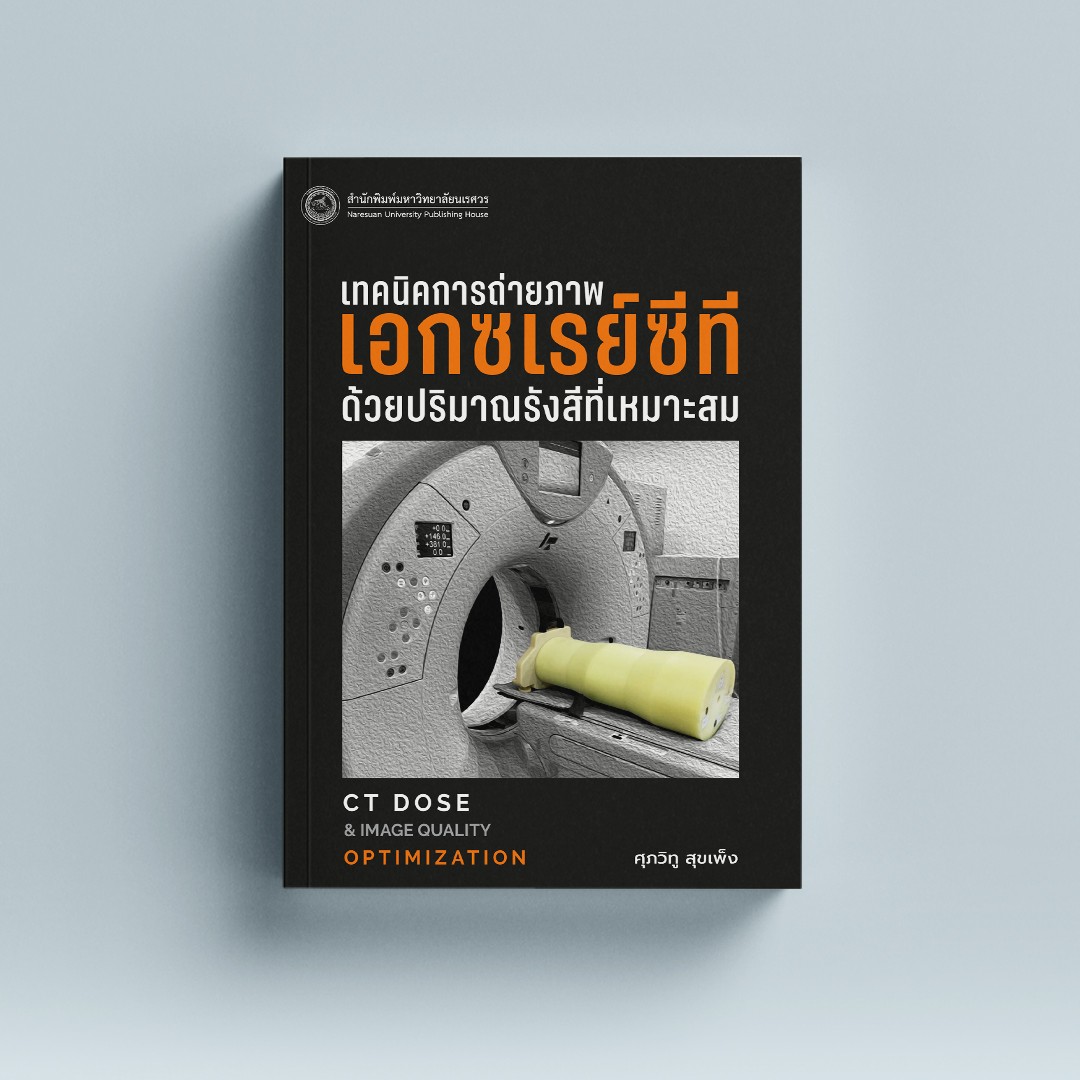

เทคนิคการถ่ายภาพเอกซเรย์ซีทีด้วยปริมาณรังสีที่เหมาะสม – ร้านหนังสือ … เทคนิคการถ่ายภาพเอกซเรย์ซีทีด้วยปริมาณรังสีที่เหมาะสม – ร้านหนังสือ …

เทคนิคการถ่ายภาพเอกซเรย์ซีทีด้วยปริมาณรังสีที่เหมาะสม – ร้านหนังสือ … สาวท้องผูกเรื้อรัง แชร์ภาพเอกซเรย์อึ้ง อ้างลำไส้บวมขยายเกือบถึงหัวใจ